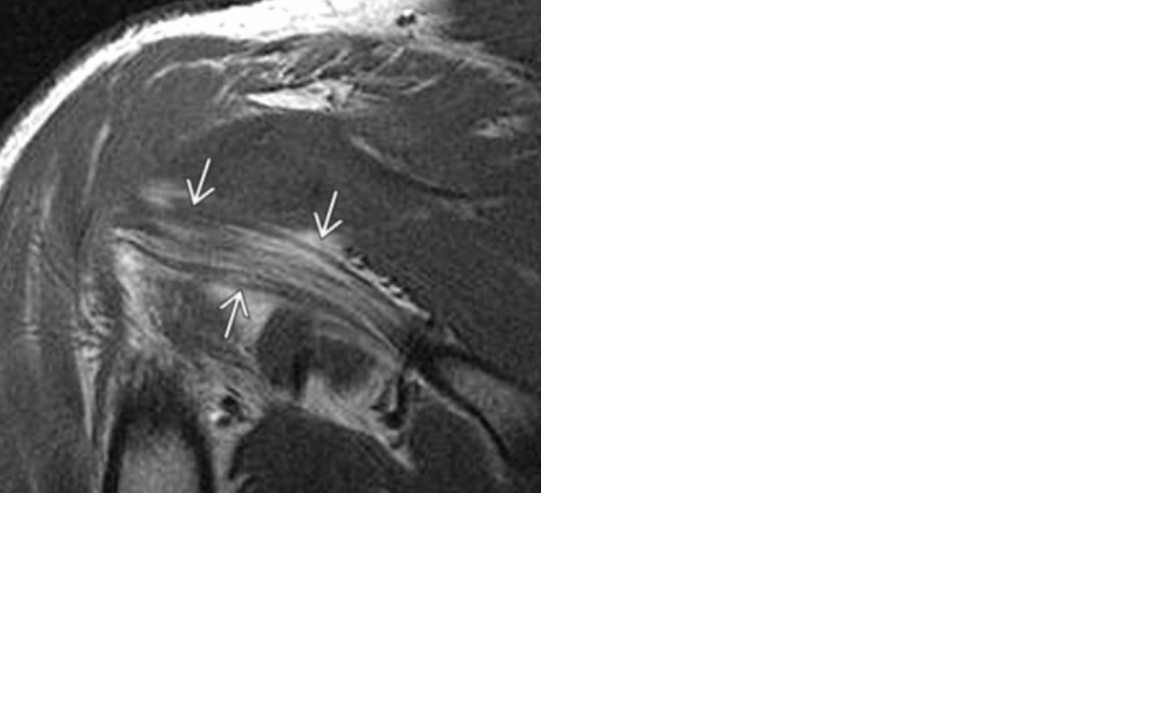

what do you think of?

Teres muscle edema: think axillary nerve pathology and

quadrilateral space syndrome